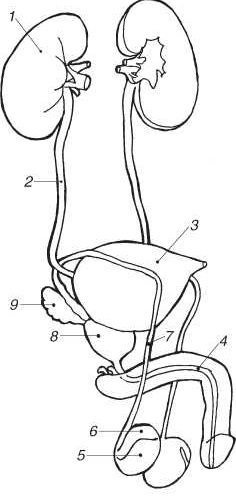

Мочеполовая система (мужская)

1 – почка; 2 – мочеточник; 3 – мочевой пузырь; 4 – мочеиспускательный канал и губчатое тело полового члена, начинающееся луковицей и заканчивающееся головкой полового члена; 5 – яичко; 6 – придаток яичка; 7 – семявыводящий проток; 8 – предстательная железа; 9 – семенные пузырьки